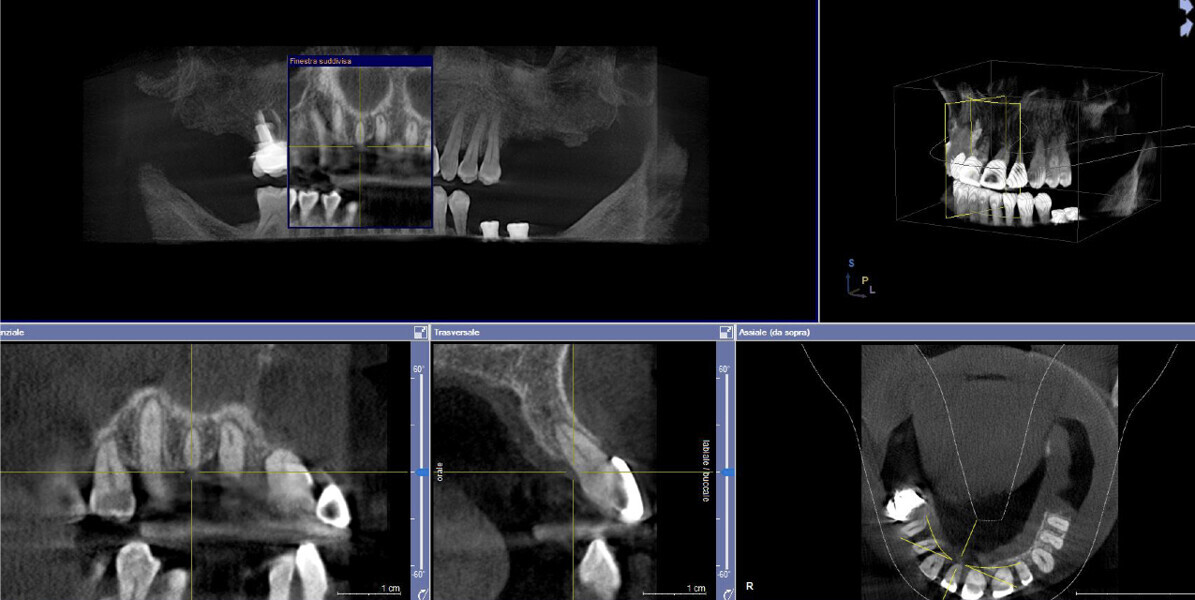

This patient, like all patients requiring interdisciplinary rehabilitation, had to first undergo periodontal treatment and caries restoration (Fig. 17). At the same time, it was important to rehabilitate swallowing with Froggymouth and relax the masticatory muscles and relieve the TMJs with an occlusal device. We could then study the orthodontic treatment plan using Invisalign ClinCheck (Align Technology) and showed the treatment plan to the interdisciplinary team and to the patient (Fig. 18). We were then able to create the correct sequence of orthodontic treatment, bone augmentation and implant surgery needed for the posterior edentulous spaces.

After the first phase of aligner treatment, we had achieved better inter-arch coherence, better maxillary arch expansion, and some space for improving the anterior tooth proportions restoratively (Fig. 19). We then temporarily restored the anterior teeth directly with composite, closing the spaces, improving the tooth proportions and further increasing the maxillary arch expansion (Fig. 20). We used restorative arch expansion to reduce the orthodontic destabilisation of the teeth to achieve the correct inter-arch coherence and retain the teeth in the cortical bone.38 A refinement aligner phase was undertaken to improve the final alignment of the gingival zenith and to improve the inter-arch coherence (Fig. 21). The periods of the first orthodontic phase and of the refinement were used to augment the mandibular and maxillary bone and to place the implants (Fig. 22). At the end of the orthodontic treatment, the case was finalised with ceramic veneers in the anterior area and temporary restorations on the implants in the posterior area (Figs. 23–26).